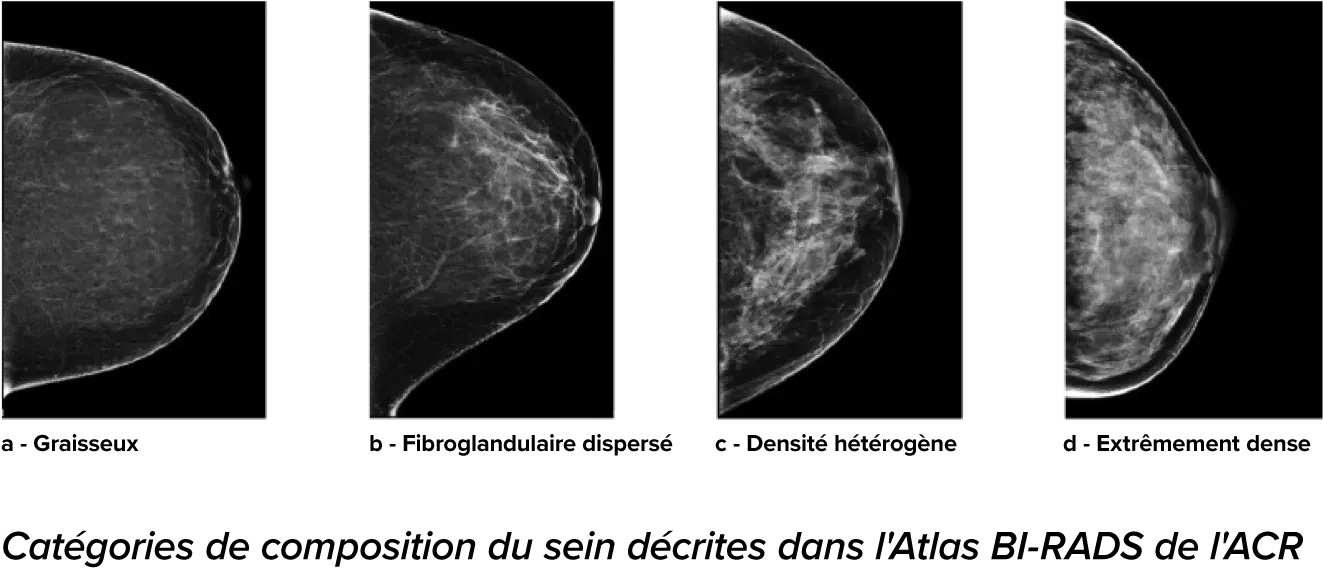

On sait qu’une densité mammaire plus élevée augmente le risque de cancer du sein chez la femme.1 Une analyse précise et objective s’avère donc primordiale. Optimisé par l’apprentissage automatique, le logiciel de la technologie Quantra analyse les images 2D™ et de tomosynthèse pour déterminer la distribution et la texture du tissu parenchymateux. Il classe les seins selon quatre catégories de composition, conformément aux recommandations de l’American College of Radiology (ACR) BI-RADS Atlas 5th Edition.2

Catégories de

risques8

8. Catégories de composition du sein décrites dans l’ACR BI-RADS Atlas.